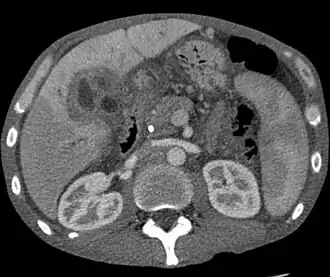

A ultrassonografia do fígado e das vias biliares é frequentemente usada como modalidade de imagem inicial em pacientes com suspeita de icterícia obstrutiva.[48][49] O ultrassom pode identificar obstrução e dilatação ductal e, em alguns casos, pode ser suficiente para diagnosticar o colangiocarcinoma.[50] A tomografia computadorizada (TC) também pode desempenhar um papel importante no diagnóstico da doença.[51][52][53]